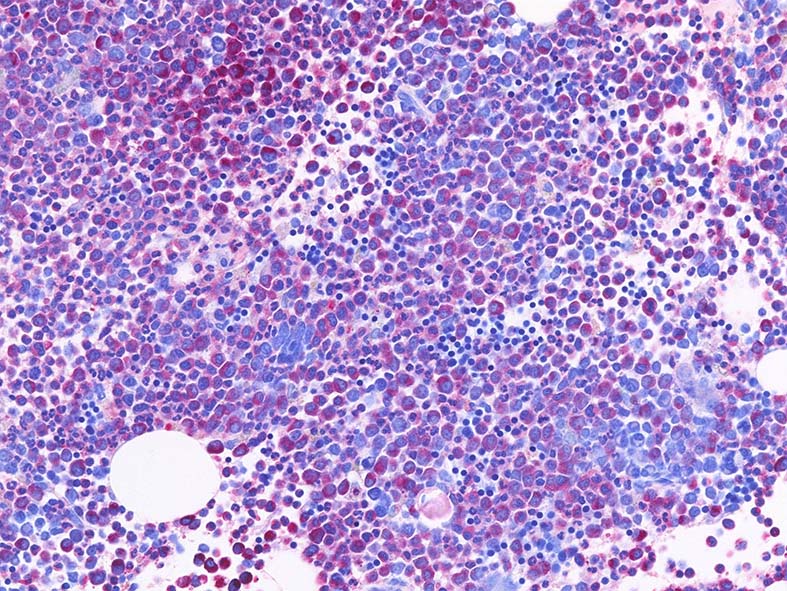

- ASD-Giemsa: 巨核球は大型であるが, 低分葉や異常な分葉, 分離核Mgkなどが認められる.

- myeloid hyper/顆粒球過形成所見がある. [ASD-Giemsaは赤く染まる細胞が増加している.]

- 成熟顆粒球への分化は認められるが, 幼若顆粒球の増多/芽球増多が認められる. 芽球は<20% (leukaemiaの基準未満)

- 赤芽球はパラパラと存在するが, 血島の形成は認めにくい.(赤芽球血島は典型的CMLにはみられないが, aCMLでは残存する.)

- cellularityが高いのに大型成熟の巨核芽球が見つけにくい.

- 多彩な巨核球がみられ, 異形成所見がある.